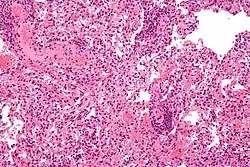

| Micrograph showing lung transplant rejection. Lung biopsy. H&E stain. | |

Acute cellular rejection occurs following direct allorecognition of mismatched donor MHC by cytotoxic T-cells that begin to secrete cytokines to recruit more lymphocytes as well as cause apoptosis or cell death directly.[4][6] The greater the difference in MHC between donor and recipient, the more cytotoxic T-cells are recruited to damage the graft,[6] which may be seen via biopsy in solid organ transplants, with increased lymphocyte infiltration indicative of more severe acute cellular rejection.[15] Acute humoral rejection is a process usually initiated by indirect allorecognition arising from recipient helper T-cells.[6] These helper T-cells have a crucial role in the development of B-cells that can create donor-specific antibodies.[4] The antibodies deposit themselves within the donor graft and lead to activation of the complement cascade alongside antibody-mediated cytotoxicity with neutrophils, a type of white blood cell separate from lymphocytes, predominantly infiltrating into tissues.[6]

Diagnosis of acute rejection relies on clinical data—patient signs and symptoms but also calls on laboratory data such as blood or even tissue biopsy. The laboratory pathologist generally seeks three main histological signs: (1) infiltrating T cells, perhaps accompanied by infiltrating eosinophils, plasma cells, and neutrophils, particularly in telltale ratios, (2) structural compromise of tissue anatomy, varying by tissue type transplanted, and (3) injury to blood vessels. Tissue biopsy is restricted, however, by sampling limitations and risks/complications of the invasive procedure.[31][32][33] Cellular magnetic resonance imaging (MRI) of immune cells radiolabeled in vivo might—similarly to Gene Expression Profiling (GEP)—offer noninvasive testing.[34][35]